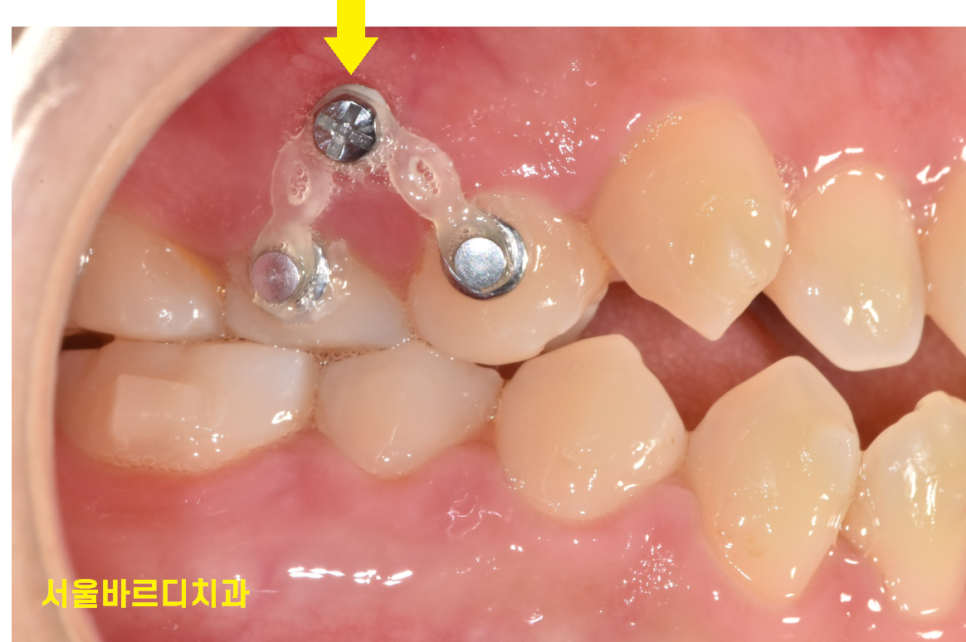

주로 잇몸 뼈 안에 삽입되어 치아를 이동 시키는데 쓰이는데요.

사진에서도 고무줄이 걸려있죠~?

미니스크류를 뼈 안에 심고

고무줄을 걸어 치아를 원하는 방향으로 당기거나 밀 때 고정원으로 사용됩니다.

뼈 안에 식립하기때문에 미니 임플란트라고도 불려요.